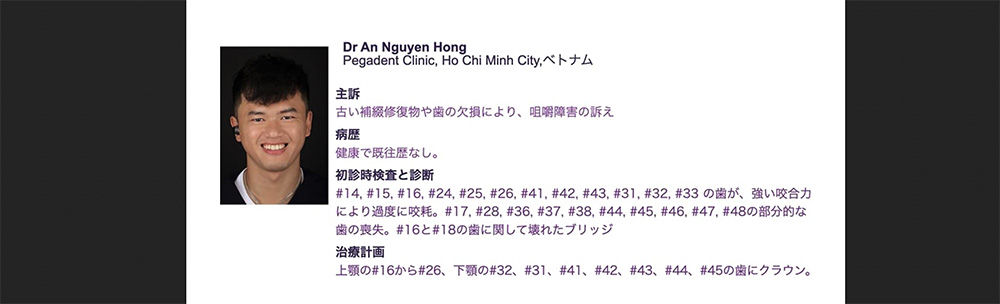

Phục hình hàm cho bệnh nhân 78 tuổi đảm bảo về thẩm mỹ và chức năng